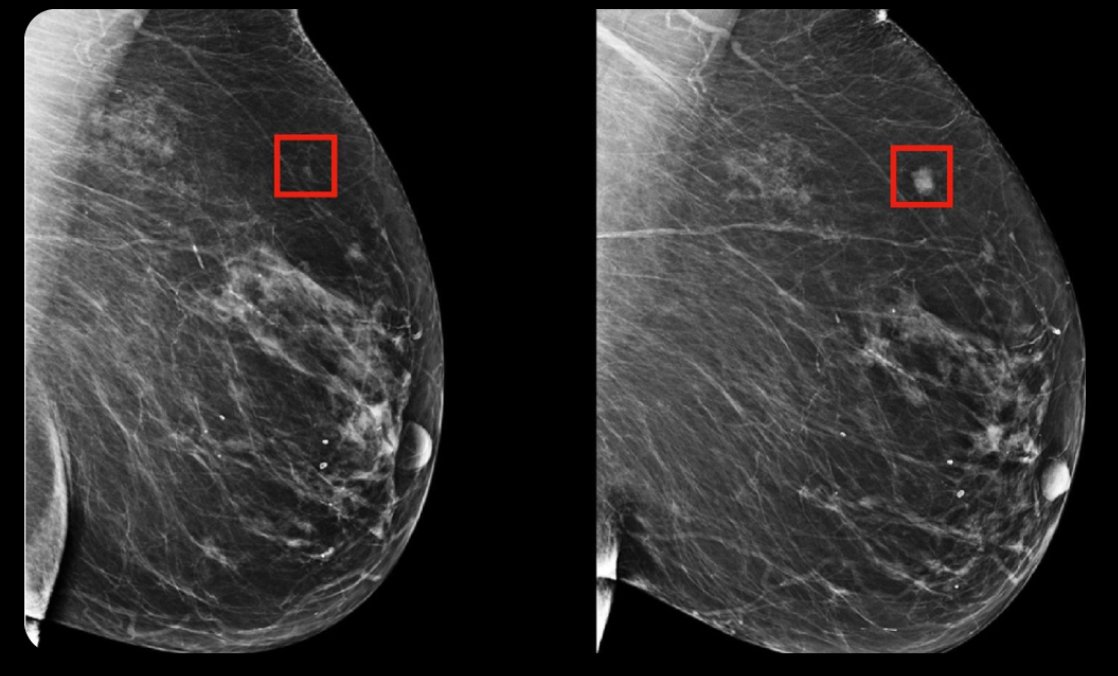

3. AI detects breast cancer 4 years before it develops.

Hungarian physicians are using an AI model that can detect breast cancer 4 years before it develops. Image